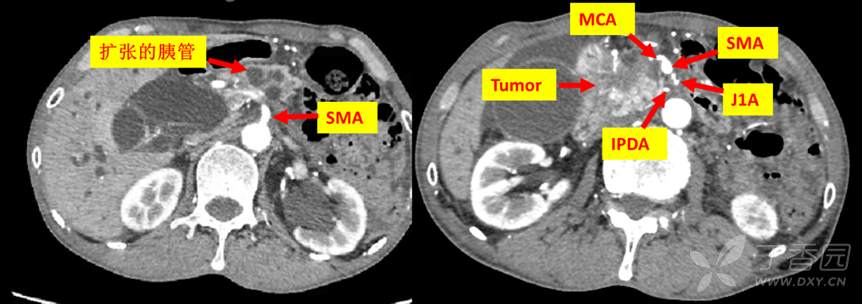

69岁男性,因纳差乏力3月,皮肤巩膜黄染2月,检查发现胰腺勾突癌入院。既往史3年前行双髋关节置换术,余无特殊。化验总胆红素121.6μmol/L,CA199:101.5U/mL。影像检查如下:

动脉系统评估,腹腔干及SMA未收侵犯,结肠中动脉可疑受侵犯。

肠系膜上静脉系统评估,结肠中静脉以下部分被肿瘤侵犯。